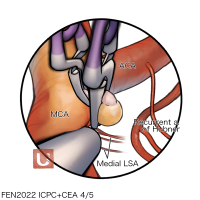

FEN2022シリーズ